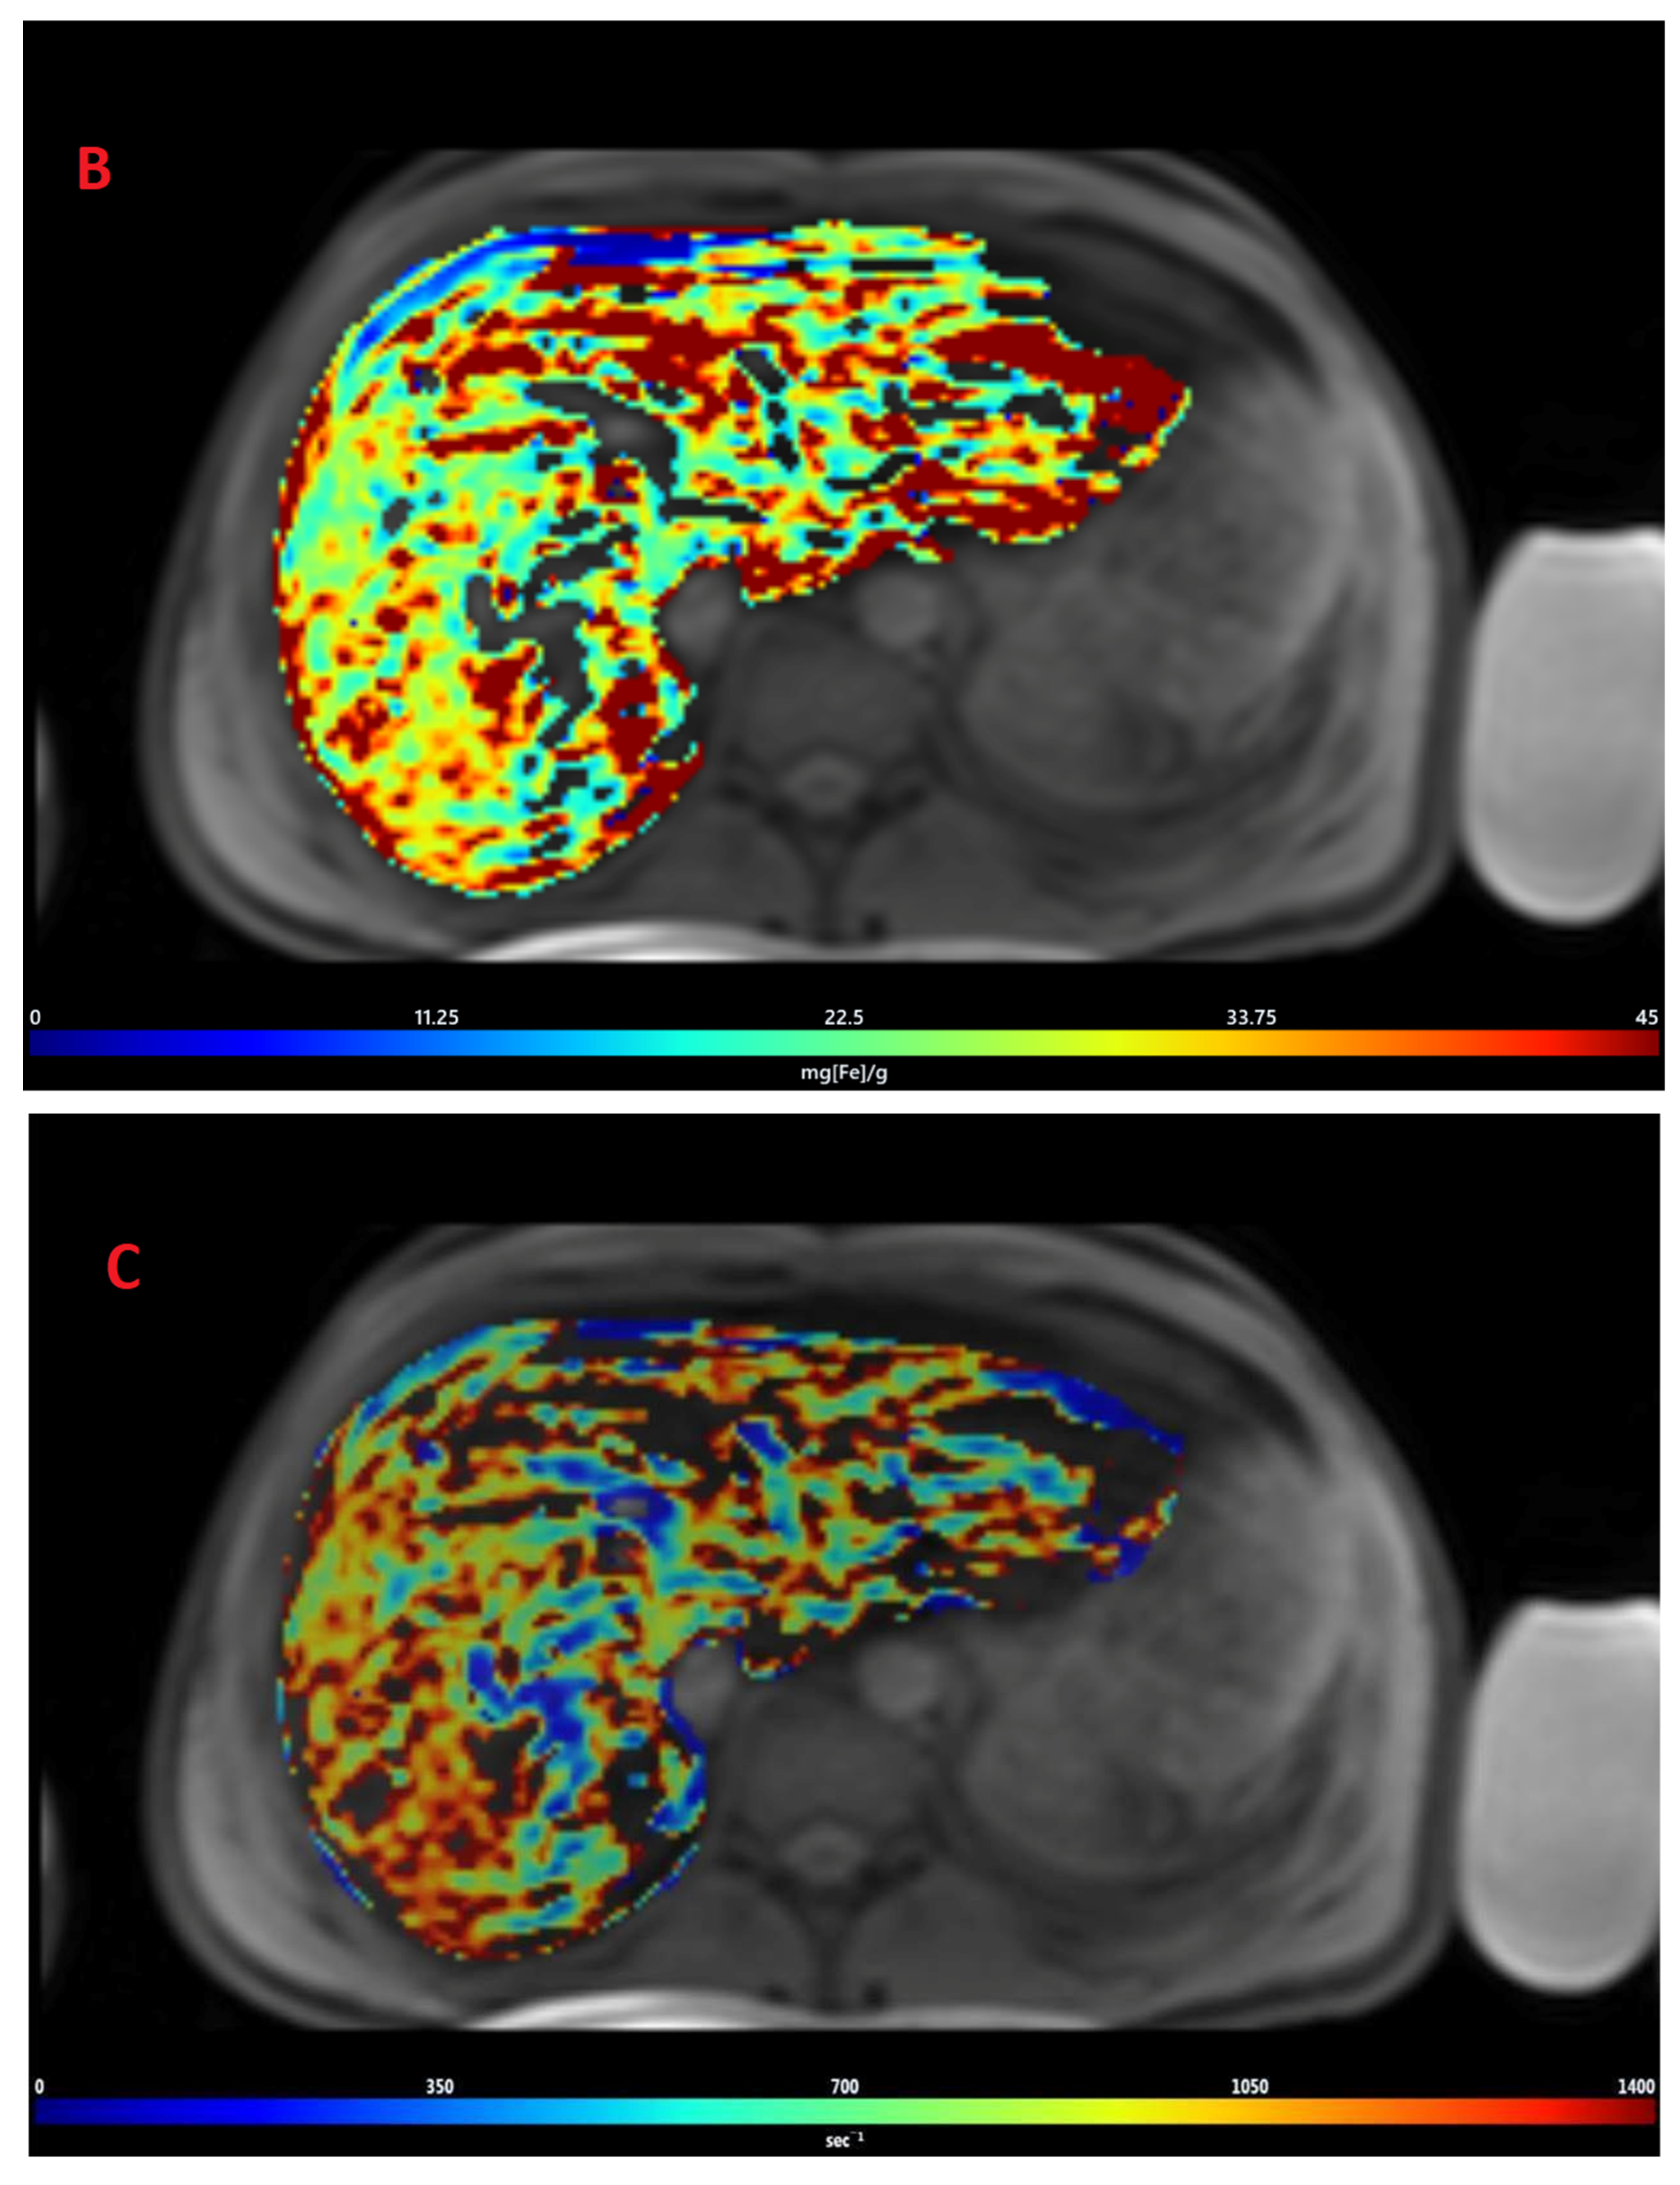

The mean value of LIC R2* at the first scan of the subjects was 10.4 ± 7.9 mg/g (range: 1.35 mg/g to 39.1 mg/g), and the mean value of R2* during the last follow-up was 8.4 ± 6.4 mg/g (range: 0.4 mg/g to 31.1 mg/g). The average rate of change of LIC determined by R2* relaxometry (∆LIC R2*) was −0.0047 ± 0.012 mg/g per month. Representative images in a patient with beta thalassemia assessed for iron overload, which provided an estimated LIC of 26.6 mg/g at time point 1 and an estimated LIC of 31.1 mg/g at time point 2 two years later, are shown in Figure 2. T2* relaxation curves for the two time points are shown in Figure 3.

Figure 2.

Representative images showing (A) the gradient axial echo slices; (B) post-processed liver iron concentration (LIC) map (color scale shows the range of LIC from 0 to 45 mg/g); and (C) R2* map in a patient with beta thalassemia assessed for iron overload at time point 1, which provided an estimated LIC of 26.6 mg/g. The lower panel (D–F) demonstrates gradient axial echo slice, post-processed LIC map, and R2* map, respectively, acquired from a scan performed after two years. The estimated LIC was 31.1 mg/g at time point 2.